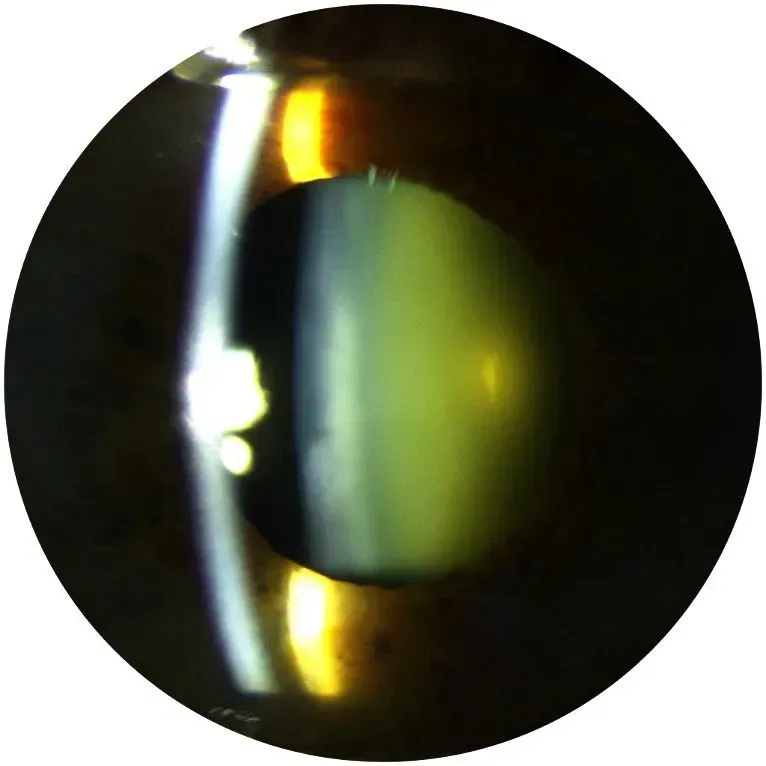

Der Graue Star

Die Augenlinse junger Menschen ist klar und transparent. Weil sich aber permanent neues Linsengewebe bildet kann die Linse mit der Zeit eintrüben. Wenn die Sehfähigkeit dadurch eingeschränkt wird, spricht man vom Grauen Star oder Katarakt.

Wenn die Linse trüb wird

Häufig tritt der altersbedingte Graue Star (Altersstar) ab einem Alter von etwa 60 Jahren auf, unter Umständen auch später oder sogar früher.

- Betroffene haben zu Beginn noch keine Beschwerden, mit fortschreitender Eintrübung machen sich jedoch Probleme in alltäglichen Situationen bemerkbar. Das Sichtfeld wirkt zunehmend verschleiert.

- Die Sehkraft lässt nach.

- Farben erscheinen weniger kräftig, Kontraste verlieren an Schärfe.

- Es kommt zu einem vermehrtem Blendgefühl

Implantation einer Kunstlinse

Der graue-gelbe Schimmer in der Mitte ist entfernt - und eine Kunstlinse ist implantiert.

Das getrübte Sehen ist vorbei und die Beschwerden von vorher sind vergessen.